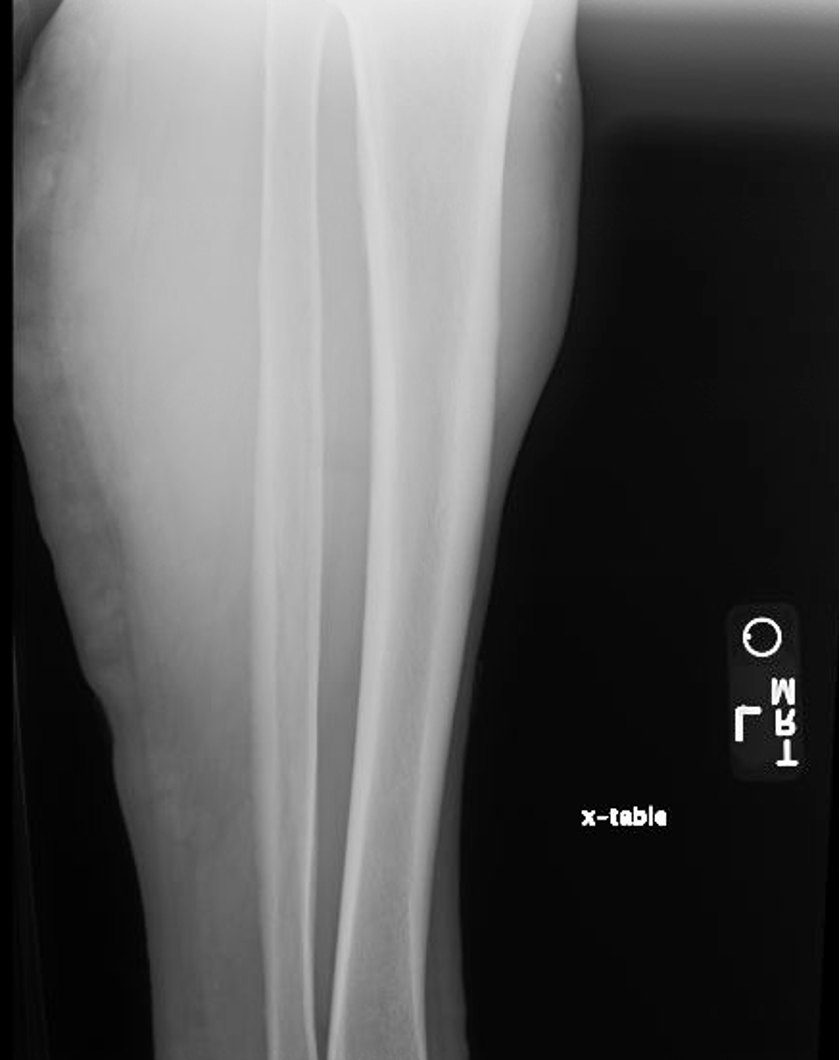

A 67-year-old man with a history of von Willebrand disease (vWD), characterized by low ristocetin cofactor to von Willebrand factor antigen ratio and hemophilia A, presented to the emergency department 3 days after a motor vehicle accident. According to the injury report, the patient's left arm was in a crossed position when his knees hit the dashboard, resulting in swelling of the soft tissues and the formation of a hematoma. A physical examination and radiographic images revealed that the patient had a left ulnar fracture, comminuted 5th metatarsal fractures on the left side, and a large hematoma on the left pretibial region measuring 15 x 6 cm with a central bulla (Figure 1). Despite the injuries, the patient had a full range of motion in all joints with gross sensation intact and could move his lower extremities without discomfort. Radiographic imaging was unremarkable for fractures or significant soft tissue damage (Figure 2).

Figure 2. Proximal pretibial soft tissue swelling without acute bony injury.